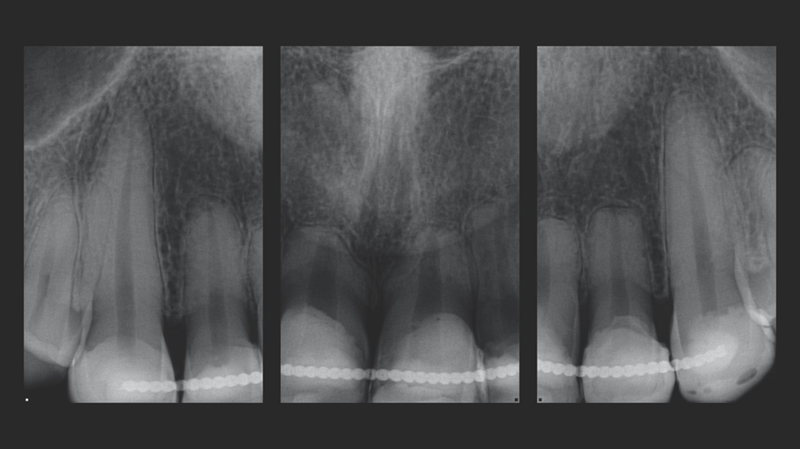

- Anamnese: Een vrouwelijke patiënt van in de 20 met een voorgeschiedenis van trauma aan de frontelementen in de bovenkaak. Ondanks het trauma bleven de gebitselementen stabiel, dus implantaten waren niet nodig.